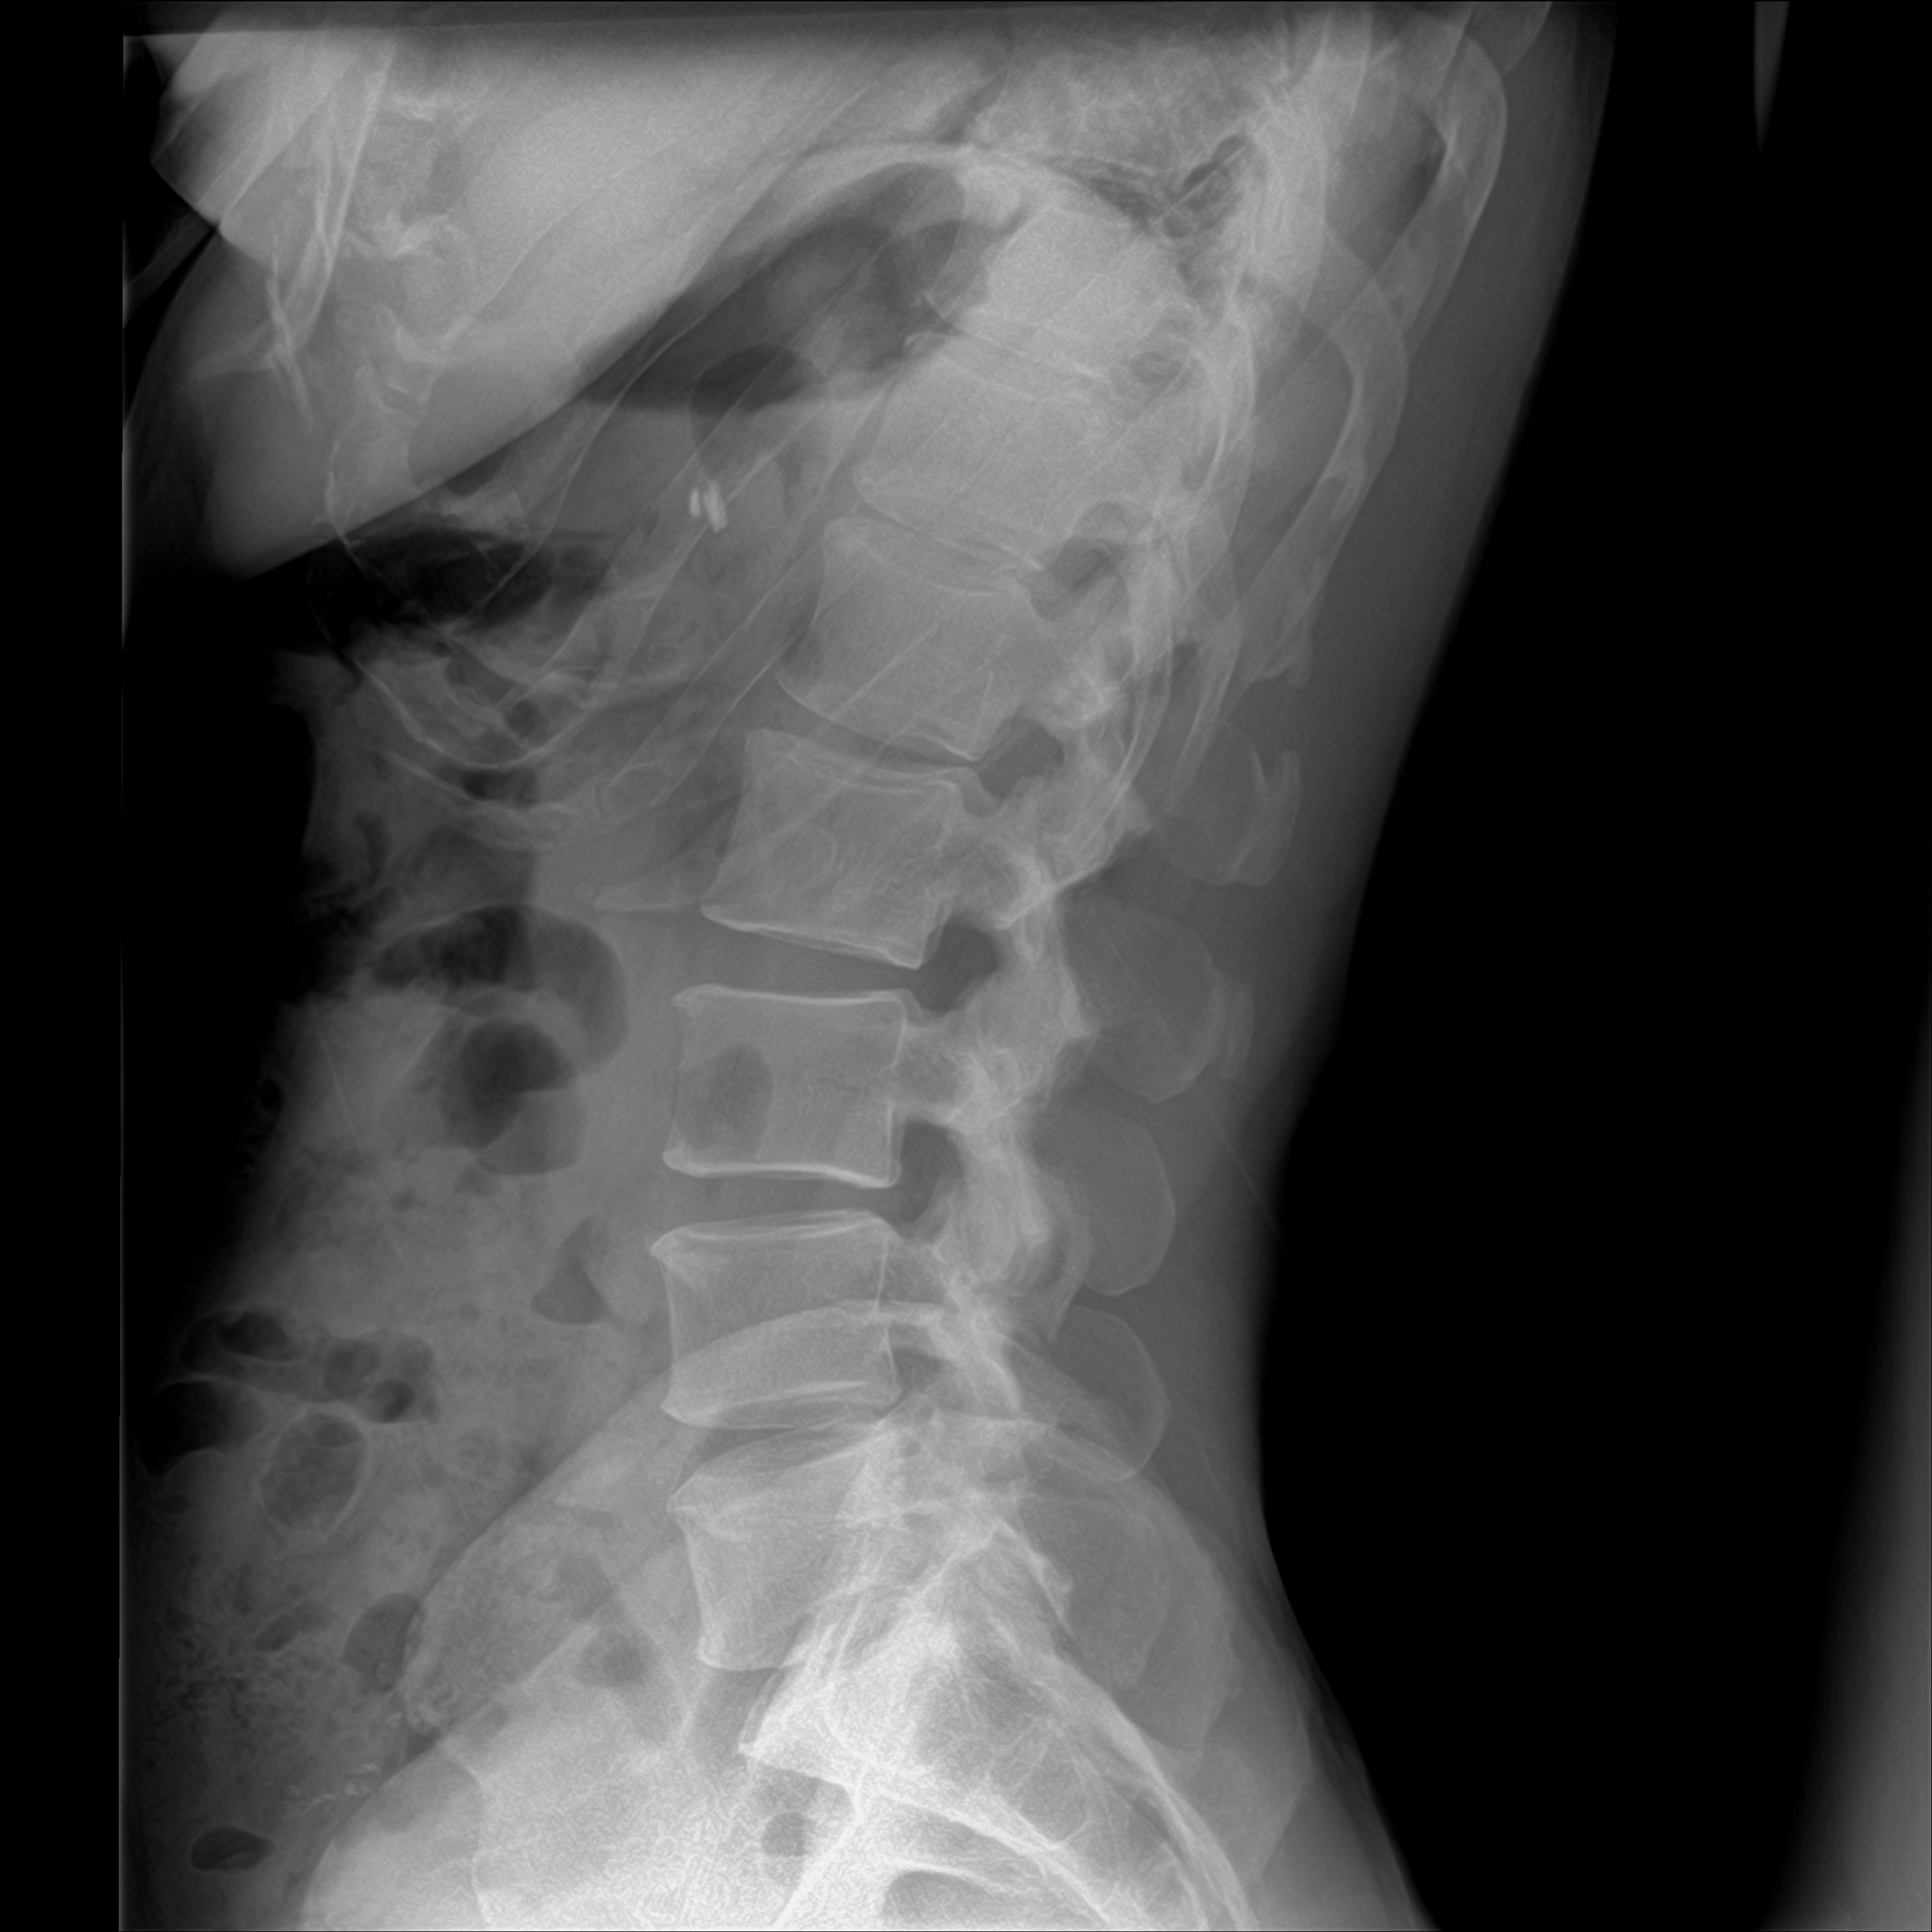

Did you know that disc degeneration affects more Americans than you might think? Degenerative Disc Disease (DDD), also commonly referred to as degenerative joint disease, is one of the most widespread spinal conditions affecting millions of Americans today. It can lead to disc bulges, herniations, or ruptures. Despite these similar-sounding names, they all point to […]

Is Your Spine Aging Faster Than You Are? What You Need to Know About Degenerative Disc Disease